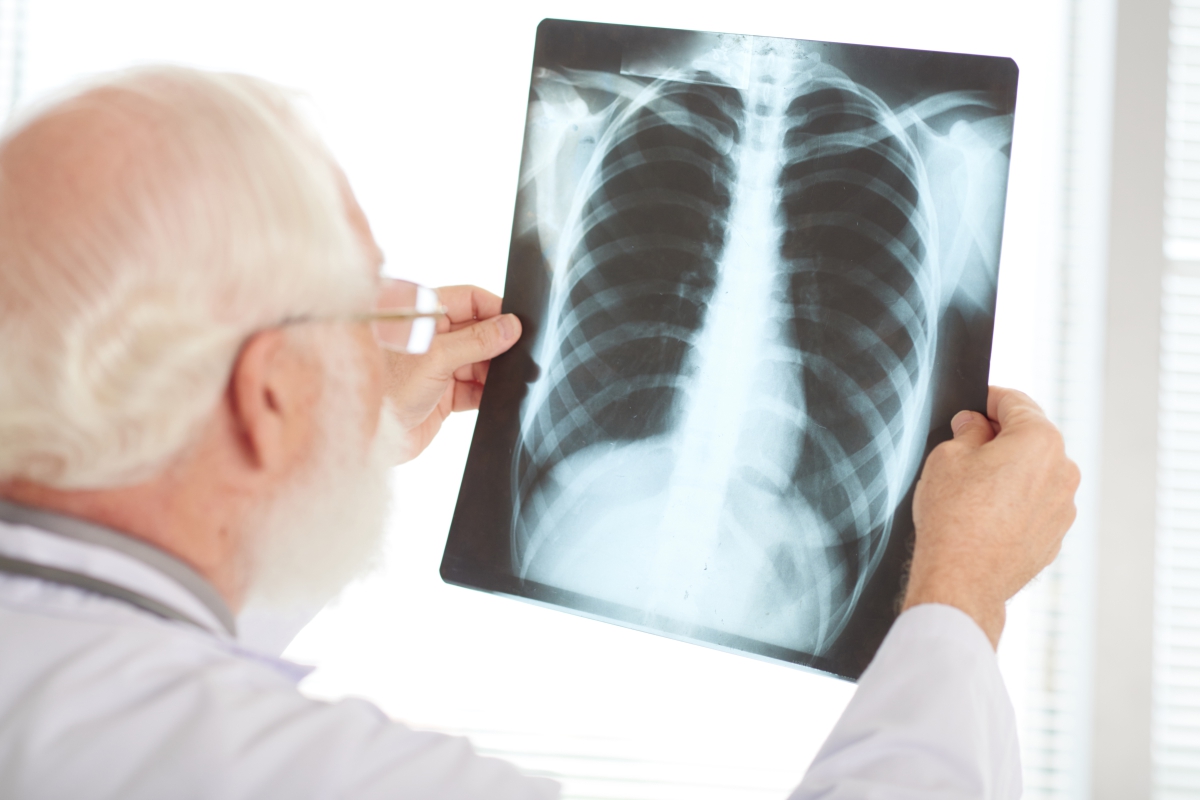

The truth is that your lungs, just like your heart, joints, and other parts of your body, age with time. They can become less flexible and lose their strength, which can make it more difficult to breathe. But by adopting certain healthy habits, you can better maintain the health of your lungs, and keep them working optimally even into your senior years.

You probably already know that smoking increases your risk of lung cancer. But that’s not the only disease it can cause. In fact, smoking is linked to most lung diseases, including COPD, idiopathic pulmonary fibrosis, and asthma. It also makes those diseases more severe.

Exposure to pollutants in the air can damage your lungs and accelerate aging. When they’re young and strong, your lungs can easily resist these toxins. As you get older, though, they lose some of that resistance and become more vulnerable to infections and disease.